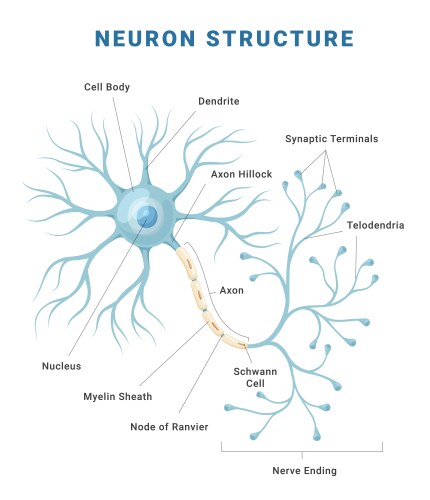

- Neuron